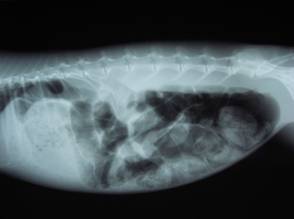

ウサギが「腸管うっ滞」をおこすと元気がなくなったり、食欲が低下したり、下痢をしたりします。

これは腸内の細菌叢に異変が起こった結果、腸内に毒素が発生して、腸毒素血症にいたる病気です。

上手に治療すれば、治りますが、この毒素が全身に回って組織壊死を起こすと死に至ります。

治療として、強制給餌や消化機能改善薬やマッサージや点滴や腸管内のガスの吸引等を行います。

原因で一番多いのは毛玉による「胃毛球症」です。